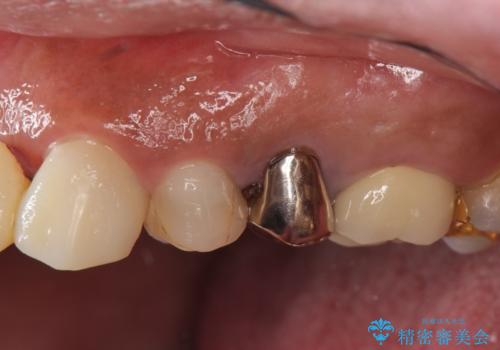

なお左上4に関しては縁下歯質を改善するため、歯冠挺出を行っております。

歯冠延長術について

歯冠長延長術とは歯肉弁根尖側移動術とも言い、歯の高さが低くクラウン(被せ物)による治療が難しい場合に、歯茎を歯根方向に下げることで歯の高さを確保する手術です。歯の高さが十分にあることで、外れにくいしっかりとしたクラウンを被せることができます。